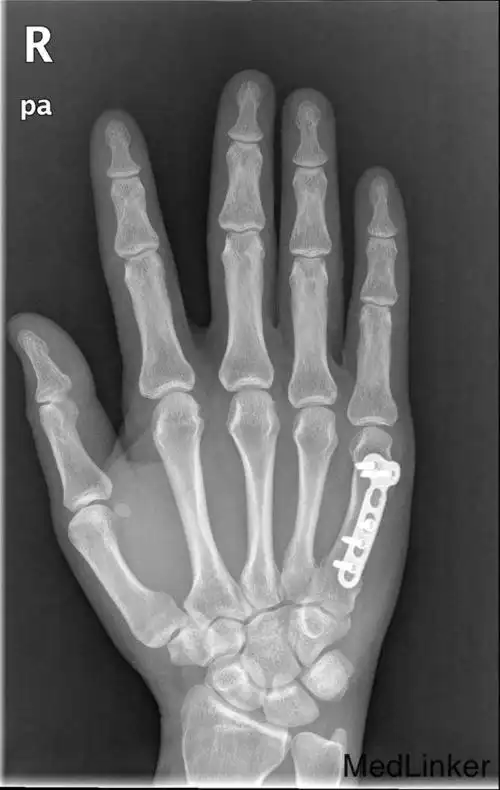

掌骨骨折